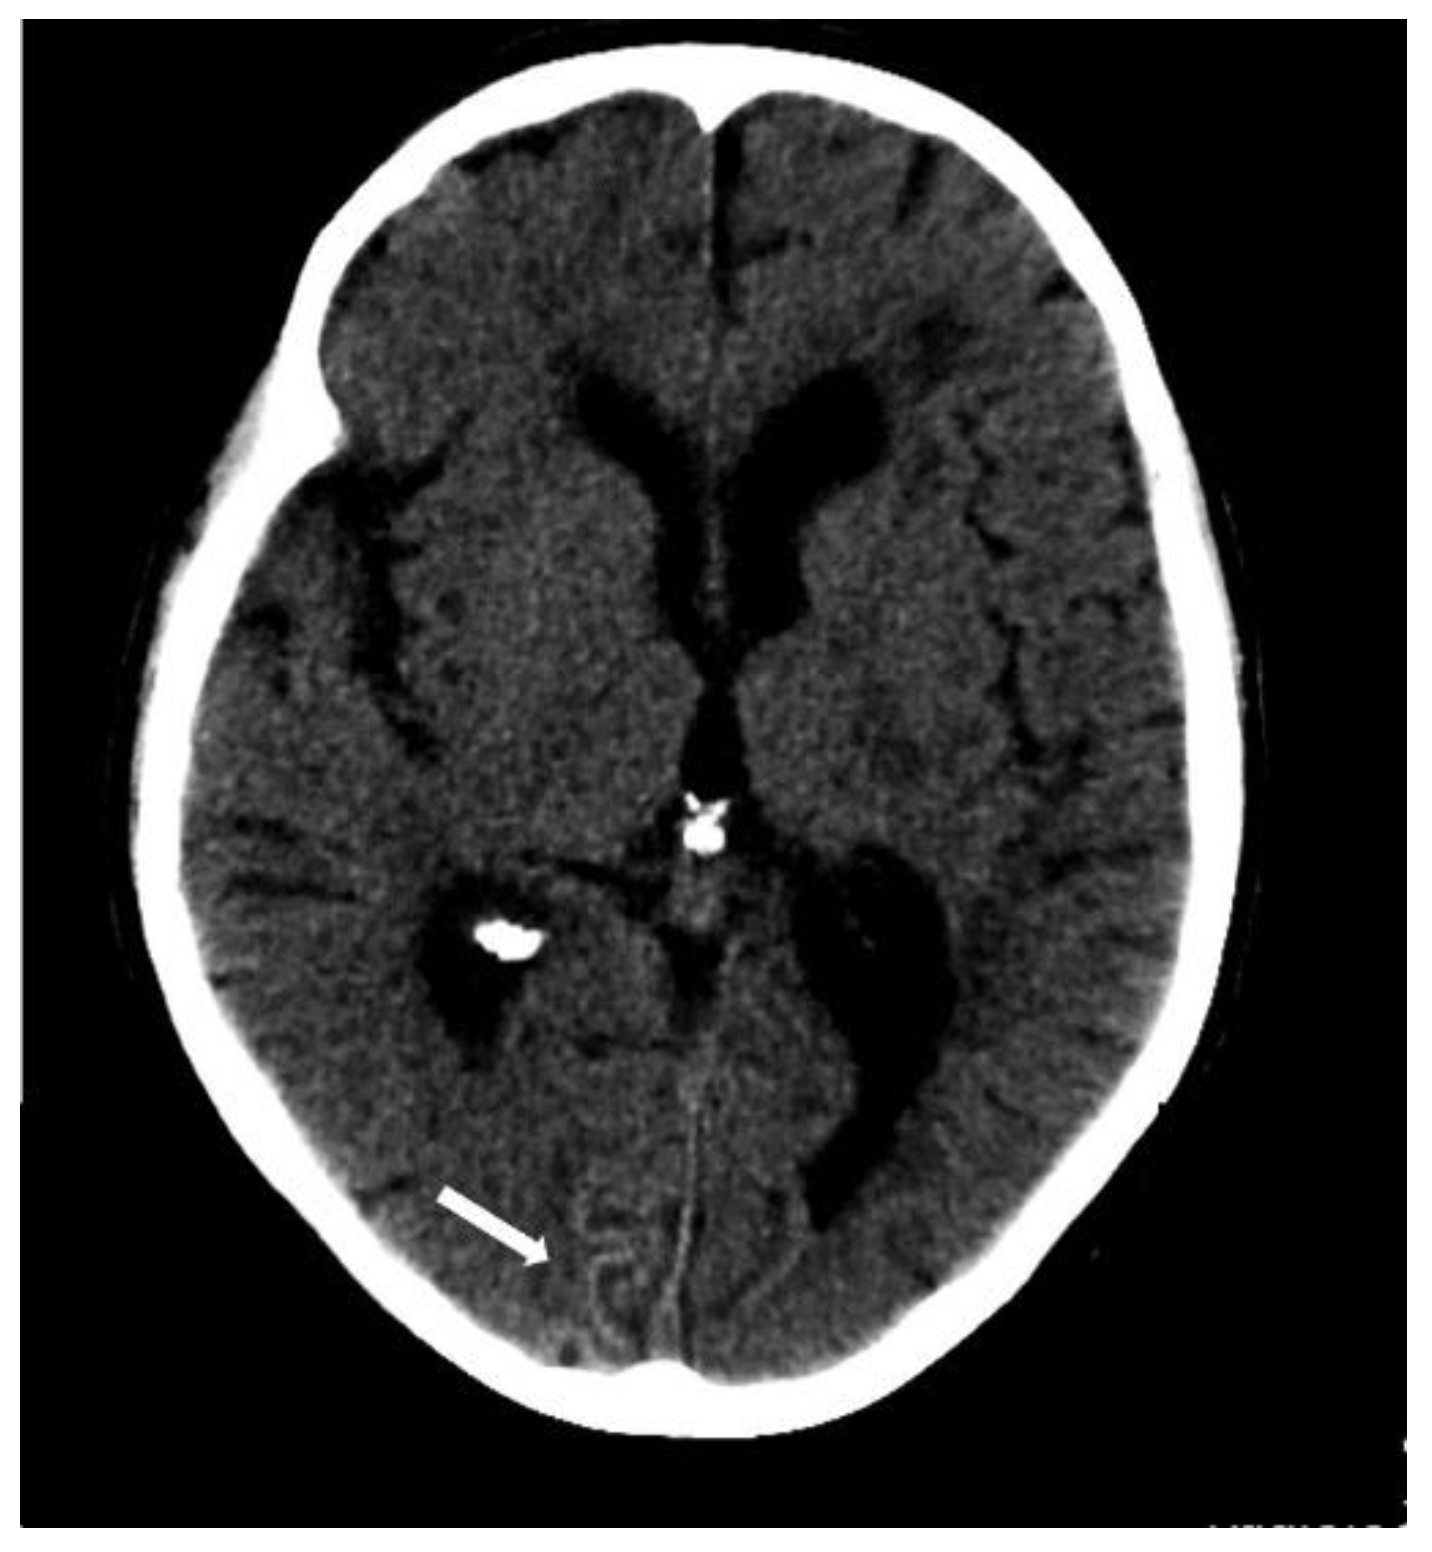

5.1.1. Lobar Hemorrhages

5.1.3. Convexity Subarachnoid Hemorrhage

5.1.4. Cortical Superficial Siderosis